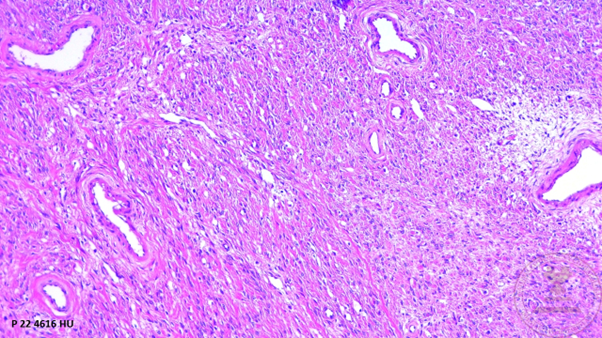

1. Panoramic view of the ovary showing the ovarian capsule, proliferation of bundles of spindle cells surrounded by a collagenous stroma accompanied by medium-caliber vessels. (HYE, 4x).

1. Proliferation of bundles of spindle cells surrounded by a collagenous stroma (H&E 10x).

1. Spindle-shaped cells with ovoid nuclei with pointed ends and scant eosinophilic cytoplasm with the presence of lipid inclusions that mixes with the surrounding eosinophilic stroma (HYE 40x).